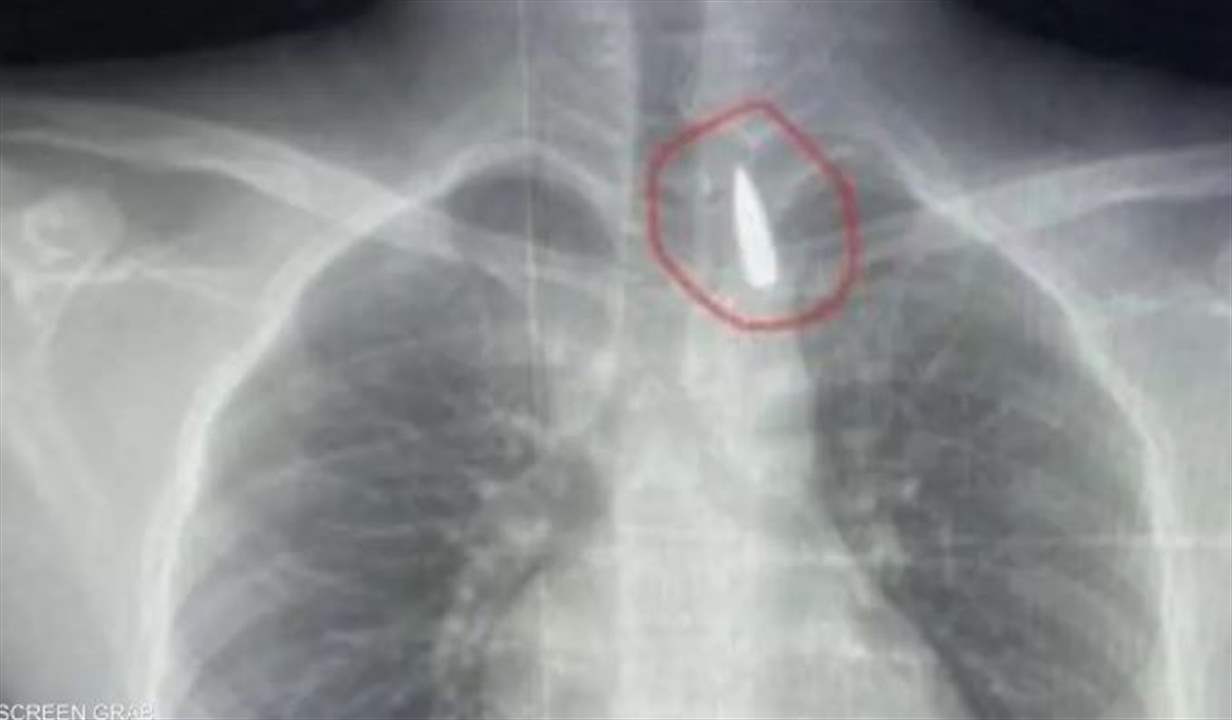

في جراحة نادرة ومعقدة.. أطباء مصريون بمشفى جامعة الإسكندرية يتمكنون من إزالة مقذوف استقر قرب الشريان الأورطي لطفل من غزة.

​الطفل تعرض لطلق ناري في الرأس فاخترق جسده واستقر المقذوف داخل تجويف القفص الصدري قرب الشريان الأورطي، أكبر وأهم شرايين الجسم والمسؤول عن تغذية جميع الأعضاء الحيوية بالجسم.